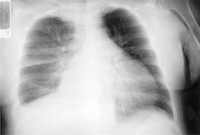

Chest x-ray showing hyperinflation in a patient with COPD. The hyperinflation is caused by the emphysema component of COPD, rather than the chronic bronchitis that underlies symptoms of cough

From the personal collection of Dr M. A. Sharifabadand, SUNY at Stony Brook School of Medicine, Department of Pulmonary and Critical Care Medicine, Mineola, New York and Dr J. P. Parsons, The Ohio State University Medical Center, Columbus; used with permission